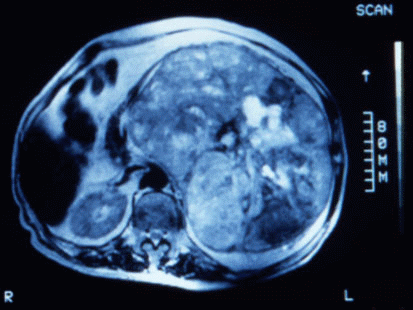

Fig. 1: Corte axial en secuencia T2 en el que se observa una gran masa, de contorno bien definido con señales heterogéneas que sugieren áreas de hemorragia y necrosis. La lesión ocupa la totalidad del hemiabdomen, cruza la línea media y desplaza las estructuras vecinas. |